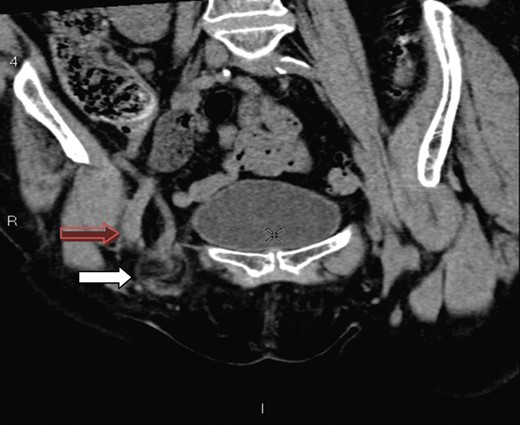

A coronal section showing the tip of the appendix (white arrow) protruding through the femoral canal, medial to femoral vein (red arrow) into the hernia. The appendix measures 10 cm.

A saggital section demonstrating the tip of the appendix (white arrow) within the femoral sac.

The presence of an appendix within the femoral canal can be explained by the presence of an abnormally low/large caecum which causes the appendix to have a pelvic location [4]. The CT findings in our patient show a very long appendix (10 cm) extending from an anatomically normal caecum with the tip extending through the femoral canal and explains another plausible mechanism for a de Garengeot's hernia. The aetiology of appendicitis has long been recognized as due to intraluminal obstruction either by a fecolith, worms, tumours or lymphoid hyrperplasia [7]. It is also possible that the rigid and narrow confines of the femoral canal can lead to extraluminal obstruction of the vermiform appendix and lead to ischaemia, inflammation, necrosis and subsequent perforation.